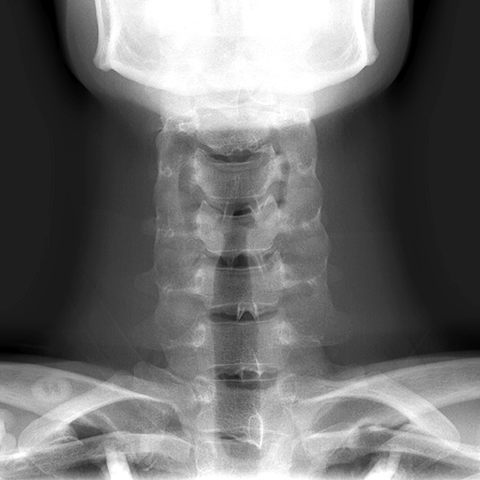

Cervical Spine, plain film (AP view) [4 of 8]